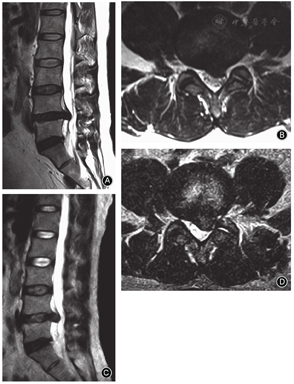

PTED在盲视下扩大椎间孔、PIED在盲视下置管均可损伤硬膜囊,内镜下摘除过程中分辨不清、盲目钳夹、突出物与硬膜囊粘连紧密也可损伤硬膜囊,导致脑脊液漏。随着PTED从椎间盘内间接减压到椎管内直接减压、以及复杂病例的增多,硬膜囊撕裂的发生率增高,大多发生在摘除阶段,但此并发症的发生率多被低估。由于经皮内镜在生理盐水压力灌洗下操作,小的撕裂神经未疝出时难以发现;较大撕裂时神经根和马尾神经也不一定马上溢出,可随水压变化而进出硬膜囊裂口。硬脊膜撕裂可导致颅内压增高,部分患者出现头痛、项背痛,甚至个别患者出现抽搐、四肢运动和感觉功能暂时性丧失等,因此,当发生硬膜囊撕裂时应尽快结束手术、降低水压,避免射频电极损伤神经纤维。由于PTED手术空间小、部位深,术后不像开放手术那样容易引起较多脑脊液漏、局部肿胀、头痛、头晕等症状;但如果神经纤维自硬膜囊破口溢出后可造成神经嵌顿或卡压,可导致剧烈的放射性疼痛,呈电击样,活动时加重,MR检查一般无明显的再突出和压迫,但可有脑脊液漏的继发影像,如神经根疝、椎间隙内脑脊液积聚等,保守治疗常无效,需开放手术探查,回纳嵌顿的神经纤维、修补缝合硬膜囊裂口。Ahn等[10]报告816例PTED患者中9例(1.1%)发生有症状的硬膜囊撕裂,但在术中发现仅3例,出现脑脊液漏和头疼、背痛,即转为开放手术修补;另6例术中未发现,术后出现腿疼,均行开放手术探查(2例神经根自硬膜囊撕裂处疝出,患者有神经损害症状,其中1例行融合手术,但随访时效果均较差;4例神经根无疝出,无神经损害症状),但其中只有2例偏外侧的撕裂可以修补,其余4例靠近中央腹侧的撕裂无法缝合,只能应用纤维蛋白胶等材料封堵填塞。

由于经皮内镜下手术中有些硬膜囊撕裂未被发现,故其实际发生率要高于术中发现率。我们有1例PTED患者术后持续性下肢放射痛,术中未发现硬膜囊撕裂,再次行可动式显微内镜椎间盘切除术(mobile MED, MMED)翻修时发现切下的关节突骨块移位、刺入硬膜囊,导致硬膜囊撕裂并卡压神经,充分减压后症状缓解[11];另1例PTED术后髓核残留的患者术中也未发现硬膜囊撕裂,行MMED再次手术时发现硬膜囊已撕裂。由于位置深、切口小,硬膜囊撕裂在经皮内镜下难以修补,撕裂较小者可用明胶海绵等封堵或旷置,为了避免神经纤维疝出,术后应尽量卧床或头低脚高位、避免硬膜囊内压力增加导致神经疝出,一般无明显症状(图3);但一旦出现神经根疝出引起下肢放射痛,往往需要开放手术进行修补。硬膜囊撕裂的危险因素包括游离型突出、大的中央型突出、粘连等。预防措施包括精确靶向穿刺和置管,一般摘除疝出及破碎髓核组织、减压充分即可,尽量保留完整的纤维环,不需常规切除后纵韧带,避免视野不清时盲目操作,更要避免过度减压和广泛暴露神经等操作。